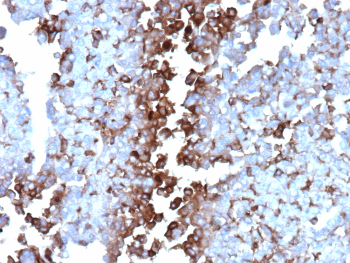

Immunohistochemistry analysis of formalin-fixed, paraffin-embedded human adrenal gland tissue using CLU/Clusterin antibody (clone CLU/4737). Predominantly cytoplasmic staining is observed in adrenal cortical cells, with variable intensity across cell populations and minimal background staining in surrounding stromal areas. Nuclei are counterstained in blue. Heat-induced antigen retrieval was performed by heating tissue sections in 10 mM Tris with 1 mM EDTA, pH 9.0, for 45 minutes at 95oC, followed by cooling at room temperature for 20 minutes.